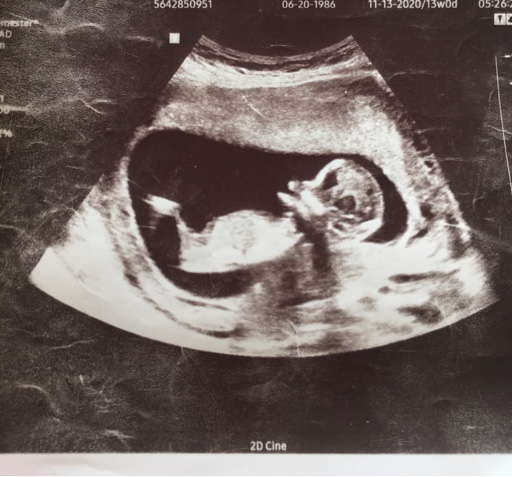

13 week ultrasound pics

Attachment 43309